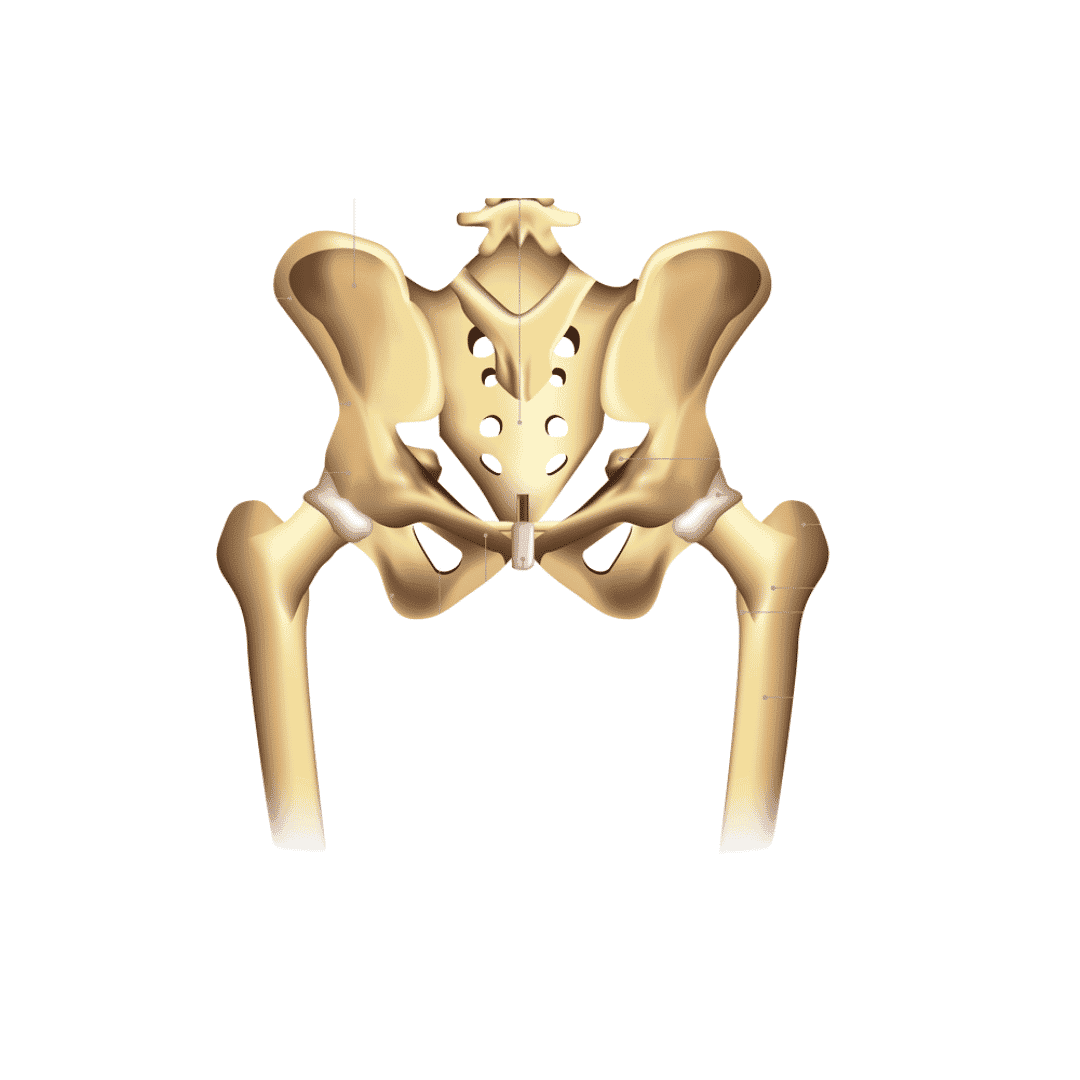

استبدال مفصل الورك الكلي (THR)

تُعدّجراحة استبدال مفصل الورك في تركيا من أكثر العمليات الجراحية رواجاً. يستخدم الجراحون عادةً أساليب جراحية طفيفة التوغل (مثل الجراحة الأمامية المباشرة) التي تحافظ على أنسجة العضلات، مما يُقلل الألم ويُسرّع الشفاء. يُمكن للمرضى الاختيار من بين غرسات عالية الجودة من السيراميك على السيراميك أو المعدن على البولي إيثيلين من كبرى الشركات العالمية المصنّعة مثل زيمر بايوميت.